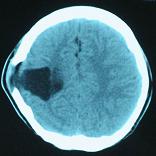

結(jié)果及隨訪:術(shù)后一周復(fù)查頭顱CT顯示腦室穿通畸形明顯縮小(圖6)。隨訪3年,未出現(xiàn)癲癇發(fā)作。得到很好的治療,回歸社會,正常生活學(xué)習(xí)工作。

圖6:術(shù)后一周復(fù)查頭顱CT顯示腦室穿通畸形明顯縮小